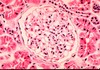

What’s seen in FM of membranous nephrotic disease?

“lighting up like Christmas trees”

diffuse - every glomerulus have granular pattern